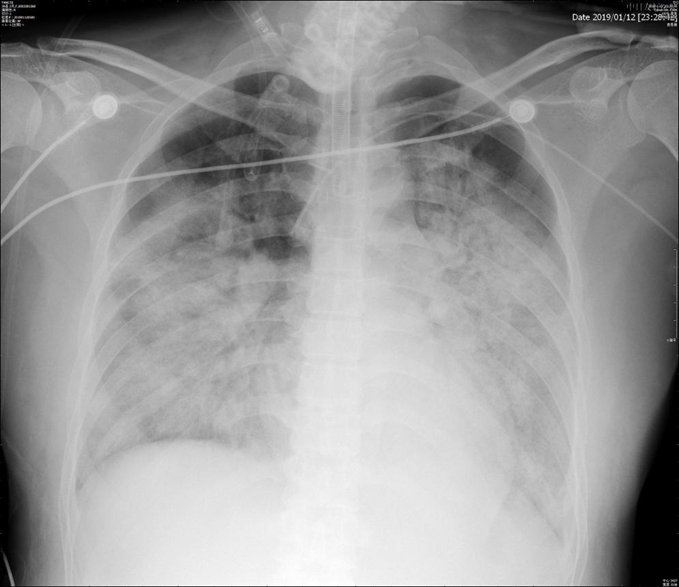

调整方案治疗后,2月2日患者有好转趋势,但在2月4日,由于患者右肺发生气胸(活检在左肺),且出现反复的高危肺栓塞(图8),最终未能抢救成功。